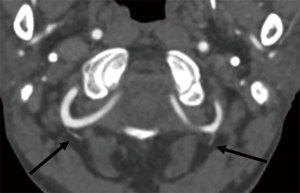

All the images were reviewed in consensus by three radiologists, each of whom had at least ten years of experience in CT diagnosis. By consulting the three-section classification criteria of V3 (13,28), we divided V3 into three subsegments: vertical portion originating from the foramen of C2, horizontal portion originating from the foramen of C1, and extradural portion originating from the posterior atlantooccipital membrane and ending at the site of piercing the dura. The three subsegments were referred to as V3v, V3h, and V3e, respectively (Figures 1-4). The number of branches was recorded. With regard to the arrangement of the branch of V3, the number 0 indicated no branches in the subsegment, and the number 1 indicated no less than one branch in the subsegment (Figure 1). There were eight kinds of arrangements of the branches altogether (000; 100; 110; 111; 010; 011; 001; 101). After an agreement was reached by consensus, all the data were confirmed. The reproducibility was assessed by comparing a subset of measurements made on 100 randomly selected cases. The radiologists were blinded to the measurements taken by the other radiologists. The 100 cases were reviewed by three observers, and interobserver agreement was calculated. All the data were imported into R statistical software, version 3.6.1, to be processed further.

Six, 8, and 7 cases were not shown in the left V3v, V3 h, and V3e, respectively, among the 668 cases. On the left, 25% (167/662), 20.21% (135/660), and 6.59% (44/661) were the frequencies of one branch in the V3v, V3h, and V3e, respectively, and 1.05% (7/662), 0.00% (0/660), and 0.45% (3/661) were the frequencies of two branches, respectively. Fourteen, 15, and 15 cases were not shown in the right V3v, V3 h, and V3e, respectively, among the 668 cases. On the right, 25.04% (167/654), 17.07% (114/653), and 6.44% (43/653) were the frequencies of one branch in the V3v, V3h, V3e, respectively, and 1.04% (7/654), 0.3% (2/653), and 0.15% (1/653) were the frequencies of two branches, respectively (Table 2).

A total of 365,115, 33, 7, 87, 7, 20, and 10 cases had the eight kinds of arrangements, the 000; 100; 110; 111; 010; 011; 001; and 101 arrangements, respectively, in the left V3v, V3h, and V3e, and 373, 126, 26, 7, 76, 5, 19, and 12 cases had these arrangements on the right. A total of 139, 44, 11, 4, 35, 2, 5, and 2 cases had the eight kinds of arrangements in the left V3v, V3h, and V3e in the females, and 226, 71, 22, 3, 52, 5, 15, 8 cases had these arrangements in the left V3v, V3h, and V3e in the males. A total of 141, 54, 5, 2, 27, 2, 9, and 2 cases had the eight kinds of arrangements in the right V3v, V3h, and V3e in the females, and 232, 72, 21, 5, 49, 3, 10, and 10 cases had these arrangements in the right V3v, V3h, and V3e in the males (Table 2). There were no differences between sex and the left side according to the two-sample KS test (P=0.942), and there were no differences between sex and the right side (P=0.8519). According to Kendall’s W test, the interobserver agreement was excellent (uncorrected for ties: 0.9802, corrected for ties: 0.9939, Spearman's ranked correlation: 0.9927).

The vertebral artery has a tortuous shape to meet the need for flexible movement and to facilitate smooth blood flow. V3 is anatomically defined as the vertebral artery that passes from the foramen of C1 to the site of the piercing dura, and it is radiologically defined as the artery passing from the foramen of C2 to the piercing site (26,27). Considering the occipito-atlantoaxial complex is a functional complex, we adopted the latter definition. The V3 that was identified was then divided into two portions demarcated by the foramen of the C1 process, namely, the horizontal and vertical portions, as reported in previous studies. In this study, we divided V3 into three subsegments, namely, the V3v, V3h, and V3e subsegments (13,29). V3e was the section passing from the posterior atlantooccipital membrane to the site of piercing the dura (28). The V3v was easily identified on CTA images. The starting point of V3e was defined as the point of intersection of the course of V3 and the superior border of C1 to which the posterior atlantooccipital membrane attached (29). The terminal point of V3e was marked by the density difference between the cerebrospinal fluid and dura mater on CTA images. The branch arising from V3h was defined as the suboccipital artery of Salmon that supplied the neighboring muscles. The frequency of the artery of Salmon was 20% in a study of 10 cadavers and 67% a study of 15 cadavers (26,27). The frequency of the artery of Salmon was 17.07–20.21% in V3h. Our results are consistent with those reported by Tubbs RS et al. Three branches arising from the V3h were discovered by dissecting cadavers (27), while no more than 2 branches were revealed in our research. The frequency of the branch was 25% in V3v and less than 6% in V3e. The rate of asymmetry in the arrangements of the branches of V3 was 30% according to the autopsy; in other words, the rate of symmetry was 70% in the arrangements (27). In our study, all eight arrangements of branches of V3 were symmetric, regardless of the sex and side of the patient. The permutation of (0,0,0) was the most frequently occurring permutation, followed by (1,0,0), and (0,1,1) was the least frequent (Table 3).